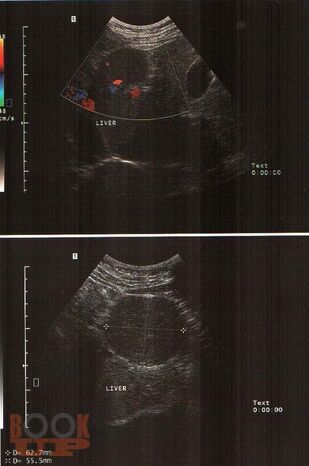

В практическом руководстве отражены вопросы ультразвуковой диагностики доброкачественных, злокачественных опухолей печени, поджелудочной железы, метастатического поражения печени, пороков развития, заболеваний гепатопанкреатодуоденальной зоны. Практическое руководство предназначено для специалистов лучевой диагностики, хирургов, онкохирургов.